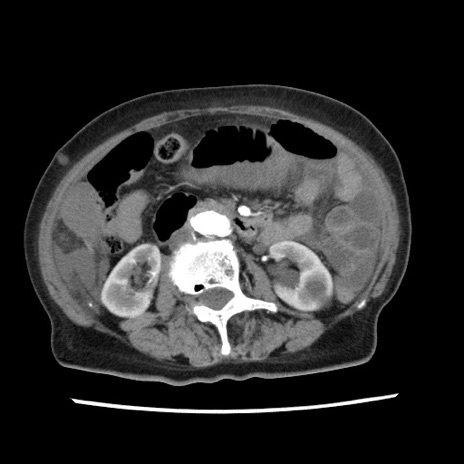

症例1(横断像)

【症例】80歳代女性

【主訴】腹痛

【現病歴】8時間前から腹痛あり来院。

【既往歴】糖尿病、脂質異常症、子宮体癌にて子宮全摘術

【身体所見】意識清明・会話良好だが腹痛で苦悶様、全腹部にわたって反跳痛と圧痛あり

【データ】WBC 13600、CRP 0.14、LDH 224、CK 90